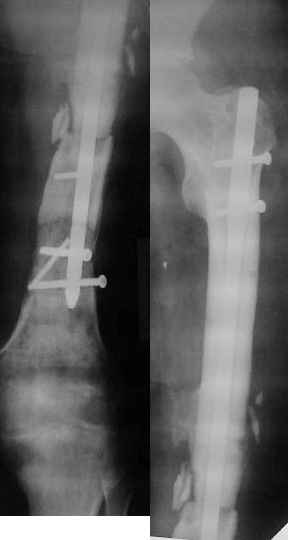

Неудачный остеосинтез пластиной: поломка винтов. После удаления сформирался гиполастический ложный сустав. Остеосинтез АВФ, циклическая компрессия-дистракция в области ложного сустава привела к формированию хорошей рентгенологической костной мозоли. Через 1,5 месяца ходил в аппарате без дополнительных средств опоры. Через 6 месяцев после клинической пробы - демотаж. Через 4 месяца после демонтажа - лизис костной мозоли, рецидив деформации.